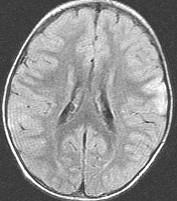

女,3岁,头痛、呕吐1周,请结合MRI图像,选择最可能的诊断是()A.脑膜炎B.硬膜下出血C.脑转移瘤D.脑梗死E.脑脓肿

问题 女,3岁,头痛、呕吐1周,请结合MRI图像,选择最可能的诊断是()

选项 A.脑膜炎 B.硬膜下出血 C.脑转移瘤 D.脑梗死 E.脑脓肿

答案 A